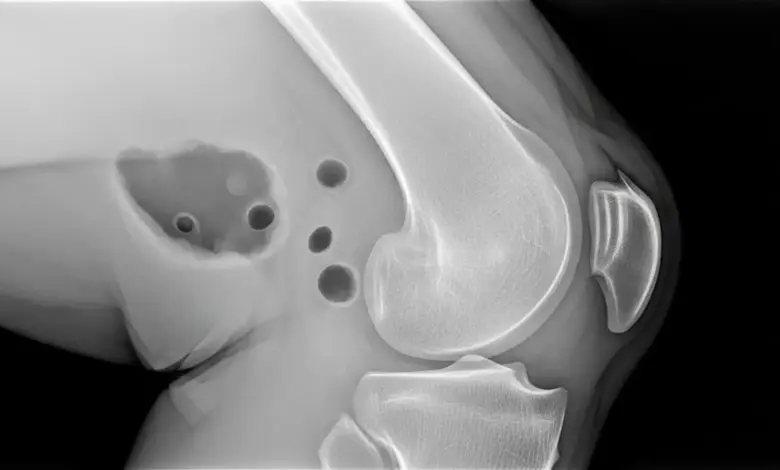

O que é a artrose do joelho

A artrose do joelho é um processo de desgaste articular. A cartilagem perde qualidade, a articulação passa a absorver pior a carga e o movimento deixa de acontecer com a mesma eficiência.

Em muitos casos, também existe inflamação local, rigidez e alteração mecânica do joelho.